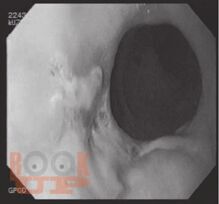

Химические ожоги пищевода и желудка

В предлагаемой читателю книге, основанной на материале клинических наблюдений более 800 больных, поступивших в НИИСП им. Н.В. Склифосовского, с позиций доказательной медицины представлены самые современные медицинские технологии эндоскопической диагностики и лечения химических ожогов пищевода и желудка.